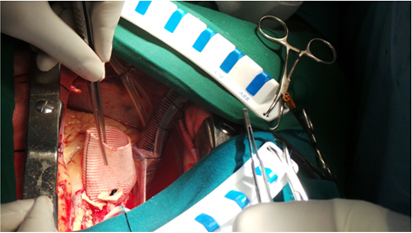

Bentals( Aortic Root Replacement ) Surgery

Surgery of Replacing The Ascending Aorta using Artificial Valved Conduit

Artificial Graft And anastomosing the Coronary Buttons